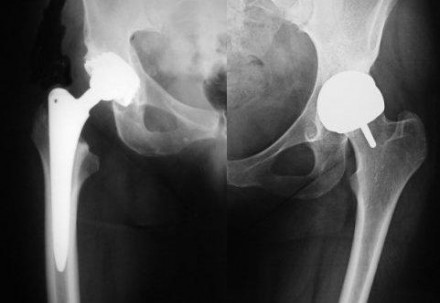

Sanità, protesi all’anca DePuy: nelle Marche utilizzate su 41 pazienti

“La Regione si è prontamente attivata per effettuare un monitoraggio completo sui pazienti coinvolti, in modo da seguire l’evolversi clinico e legale della questione“. Lo afferma il direttore del dipartimento Salute e Servizi Sociali, Carmine Ruta, al termine della riunione dedicata alla vicenda delle protesi all’anca della DePuy.